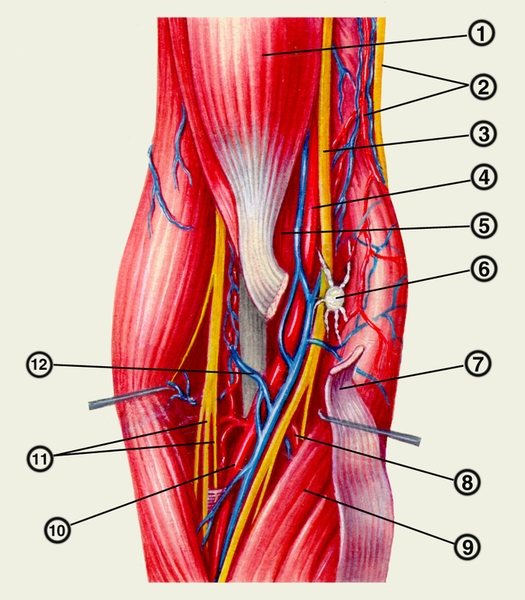

Кровоснабжение и иннервация

Чтобы локоть у человека выполнял свою функцию, ему необходима трофическая поддержка. Ни одна из вышеперечисленных структур не может существовать без адекватного кровоснабжения и иннервации. Поэтому анатомия локтевого сустава включает и эти моменты.

Локоть окружен собственной сосудистой сетью, которая образуется следующими артериями:

- Нижняя и верхняя локтевые коллатеральные.

- Лучевая и срединная коллатеральные.

- Возвратная лучевая, локтевая и межкостная.

Эти сосуды обеспечивают питательными веществами мышцы, связки, капсулу, а также синовиальную жидкость. Последняя, в свою очередь, обеспечивает трофику хрящевой ткани. Венозный отток осуществляется в локтевую, лучевую и плечевую вены. Кроме сосудистого снабжения, важна иннервация указанной зоны и прилегающих мышц. Это происходит благодаря таким нервам:

Информация о кровоснабжении локтевого сустава

К локтевому суставу кровь поступает из артериальной суставной сети локтя, на латинском она звучит, как rete articulare cubiti, которая образуется из нижней и верхней локтевой коллатеральной артерии, передней и задней ветви возвратной локтевой артерии, ветви возвратной лучевой артерии, срединной и лучевой коллатеральной артерии, а также межкостной возвратной артерии.

Кровоснабжение

Кровь приливает к суставам и мышцам с помощью сети артерий. Схема соединения сложная. Сетями плечевой, лучевой и локтевой вен проводятся кровоснабжение и отток по поверхности суставной капсулы.

Восемь веток снабжают кровью область локтя. Главные питательные вещества вовремя поступают в сустав вместе с кровотоком. Вены и ответвления наполняют кислородом, витаминами и минералами кости, мышцы и суставы. Артериальная сеть подвержена ранениям сосудов. Негативный момент: сильное кровотечение сложно остановить.

Плечевая артерия продолжает подмышечную, дает следующие ветви:

- верхнюю локтевую коллатеральную;

- нижнюю локтевую коллатеральную;

- глубокую артерию плеча, пускает ветви: среднюю коллатеральную, лучевую

- коллатеральную, дельтовидную.

Лучевая отходит с плечевой артерии в локтевую ямку, идет внизу по передней поверхности круглого пронатора, потом до середины плечелучевой мышцы, между ней и круглым пронатором, а далее по лучевым сгибателям кисти.

На протяжении артерии отходят 11 ветвей:

- лучевая возвратная артерия;

- поверхностная ладонная ветвь;

- ладонная запястная ветвь;

- тыльная запястная ветвь.

Локтевая артерия — продолжение плечевой вены, она проходит через локтевую ямку под круглым пронатором в сопровождении локтевого нерва, затем проникает в ладонь.

Ветви локтевой артерии:

- мышечные;

- локтевая возвратная;

- общая межкостная;

- ладонная запястная и глубокая ладонная.

Кровоснабжение

Кровоснабжение осуществляется через артериальную сеть, она сложена из 8 ответвлений и расположена на суставе. Эти ответвления берут начало от лучевой, локтевой и плечевой артерий. Это сочленение называется анастомозом.

Однако в этом есть и недостаток, потому что при получении травм левой или правой руки, вероятнее всего, начинается кровотечение, остановить которое бывает сложно.

Благодаря этим артериям, происходит кровоснабжение всего локтя, даже в том случае, когда перестанет выполнять свои функции одна из артерий.